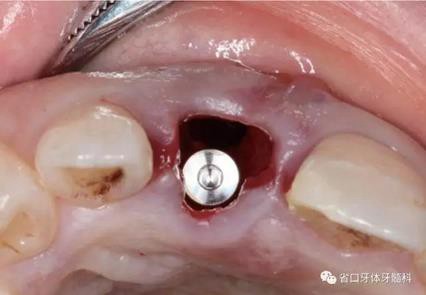

(3)術(shù)后醫(yī)囑與牙齦塑形:術(shù)后予以抗炎止痛對(duì)癥處理,7~10天拆 線。術(shù)后3個(gè)月開(kāi)始逐步調(diào)整臨時(shí)冠并塑形牙齦形態(tài),控制上頜右側(cè)中切牙 近遠(yuǎn)中牙齦乳頭的充盈量和齦緣水平,使得上頜右側(cè)中切牙牙齦形態(tài)與上頜 左側(cè)中切牙盡量相對(duì)稱。

圖26 牙齦塑形

圖27 牙齦塑形

圖28 牙齦塑形

圖29 牙齦塑形